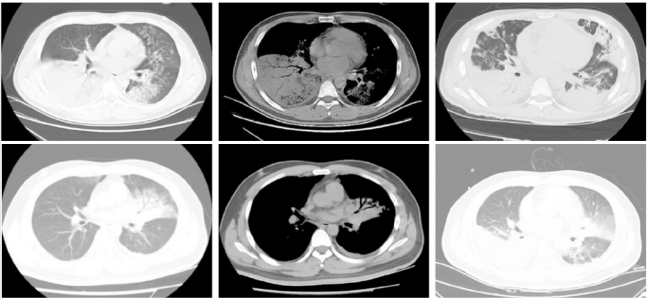

2018年1月至2020年12月我科数据显示,重症腺病毒肺炎好发于中青年男性(图2),不同病毒型的临床表现类似。图2 我科2018年1月至2020年12月重症腺病毒肺炎性别和年龄构成图重症腺病毒肺炎除了呼吸系统表现外,还会出现神经系统、循环系统、消化系统、泌尿系统、网状内皮系统及其他临床表现。呼吸系统主要表现为咳嗽、气促,发热,肺部体征出现晚,以及胸腔积液;神经系统主要表现为精神萎靡、烦躁与嗜睡交替,同时可以出现抽搐、昏迷、中毒性脑病、脑膜炎、脑水肿以及脑疝等;循环系统主要表现为心肌炎、心力衰竭、窦速,心电图T波或ST段改变;消化系统主要表现为呕吐、腹泻、中毒性肠麻痹、消化道出血;泌尿系统主要表现为蛋白尿、出血性膀胱炎;网状内皮系统可出现肝脾大、淋巴结增大表现;其他还有红色丘疹、斑丘疹、扁桃体石灰样小白点等表现。我科对重症腺病毒肺炎患者的统计分析发现,最常见的临床表现是发热、咳嗽、气促、咳痰(图3)。图3 我科2018年1月至2020年12月重症腺病毒肺炎患者症状分布直方图我科2018年1月至2020年12月重症腺病毒肺炎患者统计发现:①白细胞计数可正常,可升高(13%),也可降低(25%),淋巴细胞降低较常见(75%),血小板减少(25%);②心肌酶升高(100%):CK、CK-MB、LDH及MYO升高;③肝功能损害(56%):AST及ALT升高;④肾功能损害(25%):Cr和/或BUN升高;⑤同时存在肝肾功能损害(25%)。重症腺病毒肺炎患者胸部CT可见两下肺为主单发或多发叶段性实变伴或不伴磨玻璃影(GGO)(图4)[2]。国内文献报道了典型重症腺病毒肺炎的影像学,主要表现为实变、GGO、间质病变、胸腔积液(图5)[3]。我科统计重症腺病毒肺炎患者的影像学情况(图6):①双肺实变12例(80%),实变累及5个肺叶1例、累及4个肺叶5例、累及3个肺叶5例。②双肺实变伴GGO 5例(30%);③单肺实变3例(20%),均累及2个肺叶;④单肺实变伴GGO 3例(20%);⑤伴胸腔积液4例(25%),伴气胸1例(6%)。(1)症状:好发于中青年男性,有发热、咳嗽、呼吸困难、肌痛等表现。(2)影像学:实变伴或不伴GGO,伴胸腔积液;动态变化反映病情。